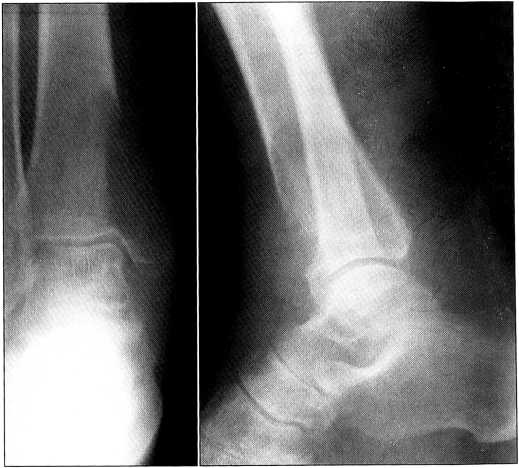

При обследовании определяется опухолевидное образование по передненаружной поверхности нижней трети правого бедра 8x6 см. На рентгенограммах на границе нижней и средней трети бедра (рис. 4, а) выявляется обширное мягкотканное опухолевидное образование полуовальной формы с краевой остеолитической деструкцией диафиза бедренной кости, захватывающей практически весь ее поперечник, с разрушением коркового слоя на протяжении 10 см. По задней поверхности бедренной кости корковый слой неровный и несколько нечеткий. На уровне костного дефекта в мягких тканях определяется дополнительная тень повышенной плотности. Заключение: рентгенологическую картину следует дифференцировать между злокачественной опухолью мягких тканей, прорастающей в бедренную кость, и метастазом. Угроза патологического перелома.

При дальнейшем обследовании у больного выявлен рак почки. Биопсия опухоли бедра подтвердила метастаз рака почки. При сцинтиграфии скелета других очагов повышенного накопления радиофармпрепарата не обнаружено и метастаз признан солитарным. В связи с возникшим патологическим переломом бедренной кости и выраженным болевым синдромом на первом этапе лечения больному 18.06.99 произведена экзартикуляция бедра, а 15.07.99 — нефрэктомия. Послеоперационный период протекал без осложнений, и через полтора месяца больной вернулся к работе (профессор кафедры). Через 9 мес выявлен метастаз в проксимальном отделе другой бедренной кости, и 15.03.00 с целью улучшения качества жизни больному произведена еще одна операция — резекция проксимального суставного конца бедренной кости с эндопротезированием (рис. 4, б, в). Послеоперационный период протекал без осложнений. После выписки пациент продолжал работать.

Рис. 4. Рентгенограммы больного К. а — правое бедро до операции; б — левое бедро до, в — после операции.